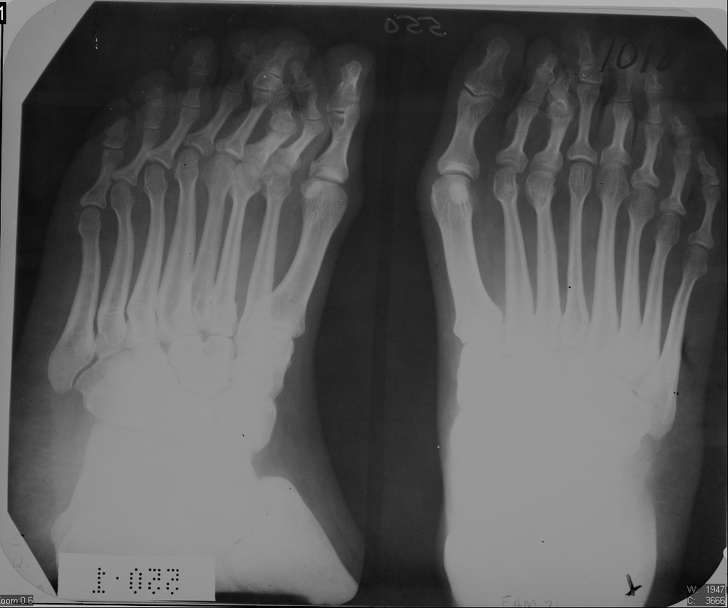

多指患者的脚部X射线照片